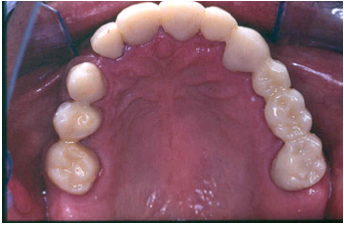

The final preparations were observed in two study casts to improve the parallelism and ensure accurate path of the insertion for the final prostheses. Final preparations and relining of the provisional restorations followed. Final impressions were performed using polyvinyl-siloxane (Aquasil, Dentsply, Germany) with the two-step double mixing technique (stock tray, double cord technique) in the maxilla. Mandibular impression was performed with an open tray technique combining implant and teeth abutments with polyether material (Impregum, 3M, USA). In next appointment the accuracy of final casts was examined and jaw relation recordings were performed. The position of maxillary cast was transferred with a Whip-Mix face bow and centric relation (CR) was registered with a custom made acrylic Lucia jig (anterior deprogrammer) and an implant retained base plate in the mandible to ensure accurate registration. Dental and implant abutments metal try-in were completed in two steps (Figure 16). After thorough verification of accuracy of fit and jaw registrations, ceramic veneering was checked for proper occlusion (Figure 17,18). Finally all restorations were cemented with adhesive resin cement (Panavia F2.0, Kuraray, Japan), except for the implant restorations which were cemented with a provisional cement (Temp-bond, Kerr, Germany).

Figure 17: Final restorations occlusal view of the maxilla.